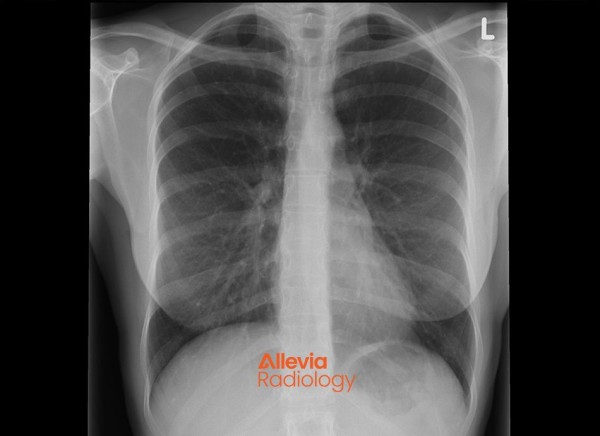

A chest X-ray is a ‘picture’ that shows the ribs, lungs, diaphragm and size of the heart.

- When someone is acutely unwell with shortness of breath, fever and cough, a chest X-ray might be ordered to look for signs of infection, (such as pneumonia) inflammation, fluid build-up in the lungs or tumours or masses.

- It's often used to assess people who have smoked for many years to look for signs of chronic lung disease and lung cancer.

- A chest X-ray is also often done before an operation to check your lungs and heart appear normal.

Image credit: Allevia Radiology

- Structures containing air will be black, and muscle, fat, and fluid will appear as shades of grey.